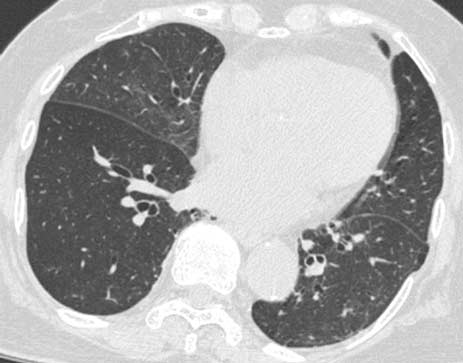

“疑云重重”:医生初步怀疑患者为支气管哮喘,给予吸入糖皮质激素和长效β受体激动剂治疗,此后症状得到缓解。但CT表现在4个月后恶化(图2A, B)。疑似为肺泡蛋白沉积症(pulmonary alveolar proteinosis,PAP),进一步行支气管镜检查。支气管肺泡灌洗液呈浑浊白色液体,随后由PAP专家进一步评估。

图2 随访胸部CT图像。A和B. 4个月后的CT示右中叶和双下叶GGO(箭头),伴小叶间隔增厚(箭头);C.5个月后CT示GGO,双侧下叶(圈子)出现新的小叶中心结节。

“拨云见日”:转诊至上一级医院,5个月后患者CT检查示GGO,双侧下叶出现新的小叶中心结节(图2C)。抗粒细胞-巨噬细胞集落刺激因子抗体证实为阴性。这些结果提示可能为外源性类脂性肺炎(exogenous lipoid pneumonia,ELP)。因此,再次仔细回顾患者社会史发现,患者在电视节目中了解到“油拔法”(源于印度民间的保健方法,将食用油在口腔内旋转一段时间,然后吐出来,类似于漱口),于是每天用芝麻油漱口数次,希望美化嗓音。根据CT表现并结合其生活习惯,医生怀疑患者吸入了芝麻油,并进行吞咽造影检查。用液体漱口时,发现液体进入梨状窝,提示患者可能因芝麻油漱口而误吸。